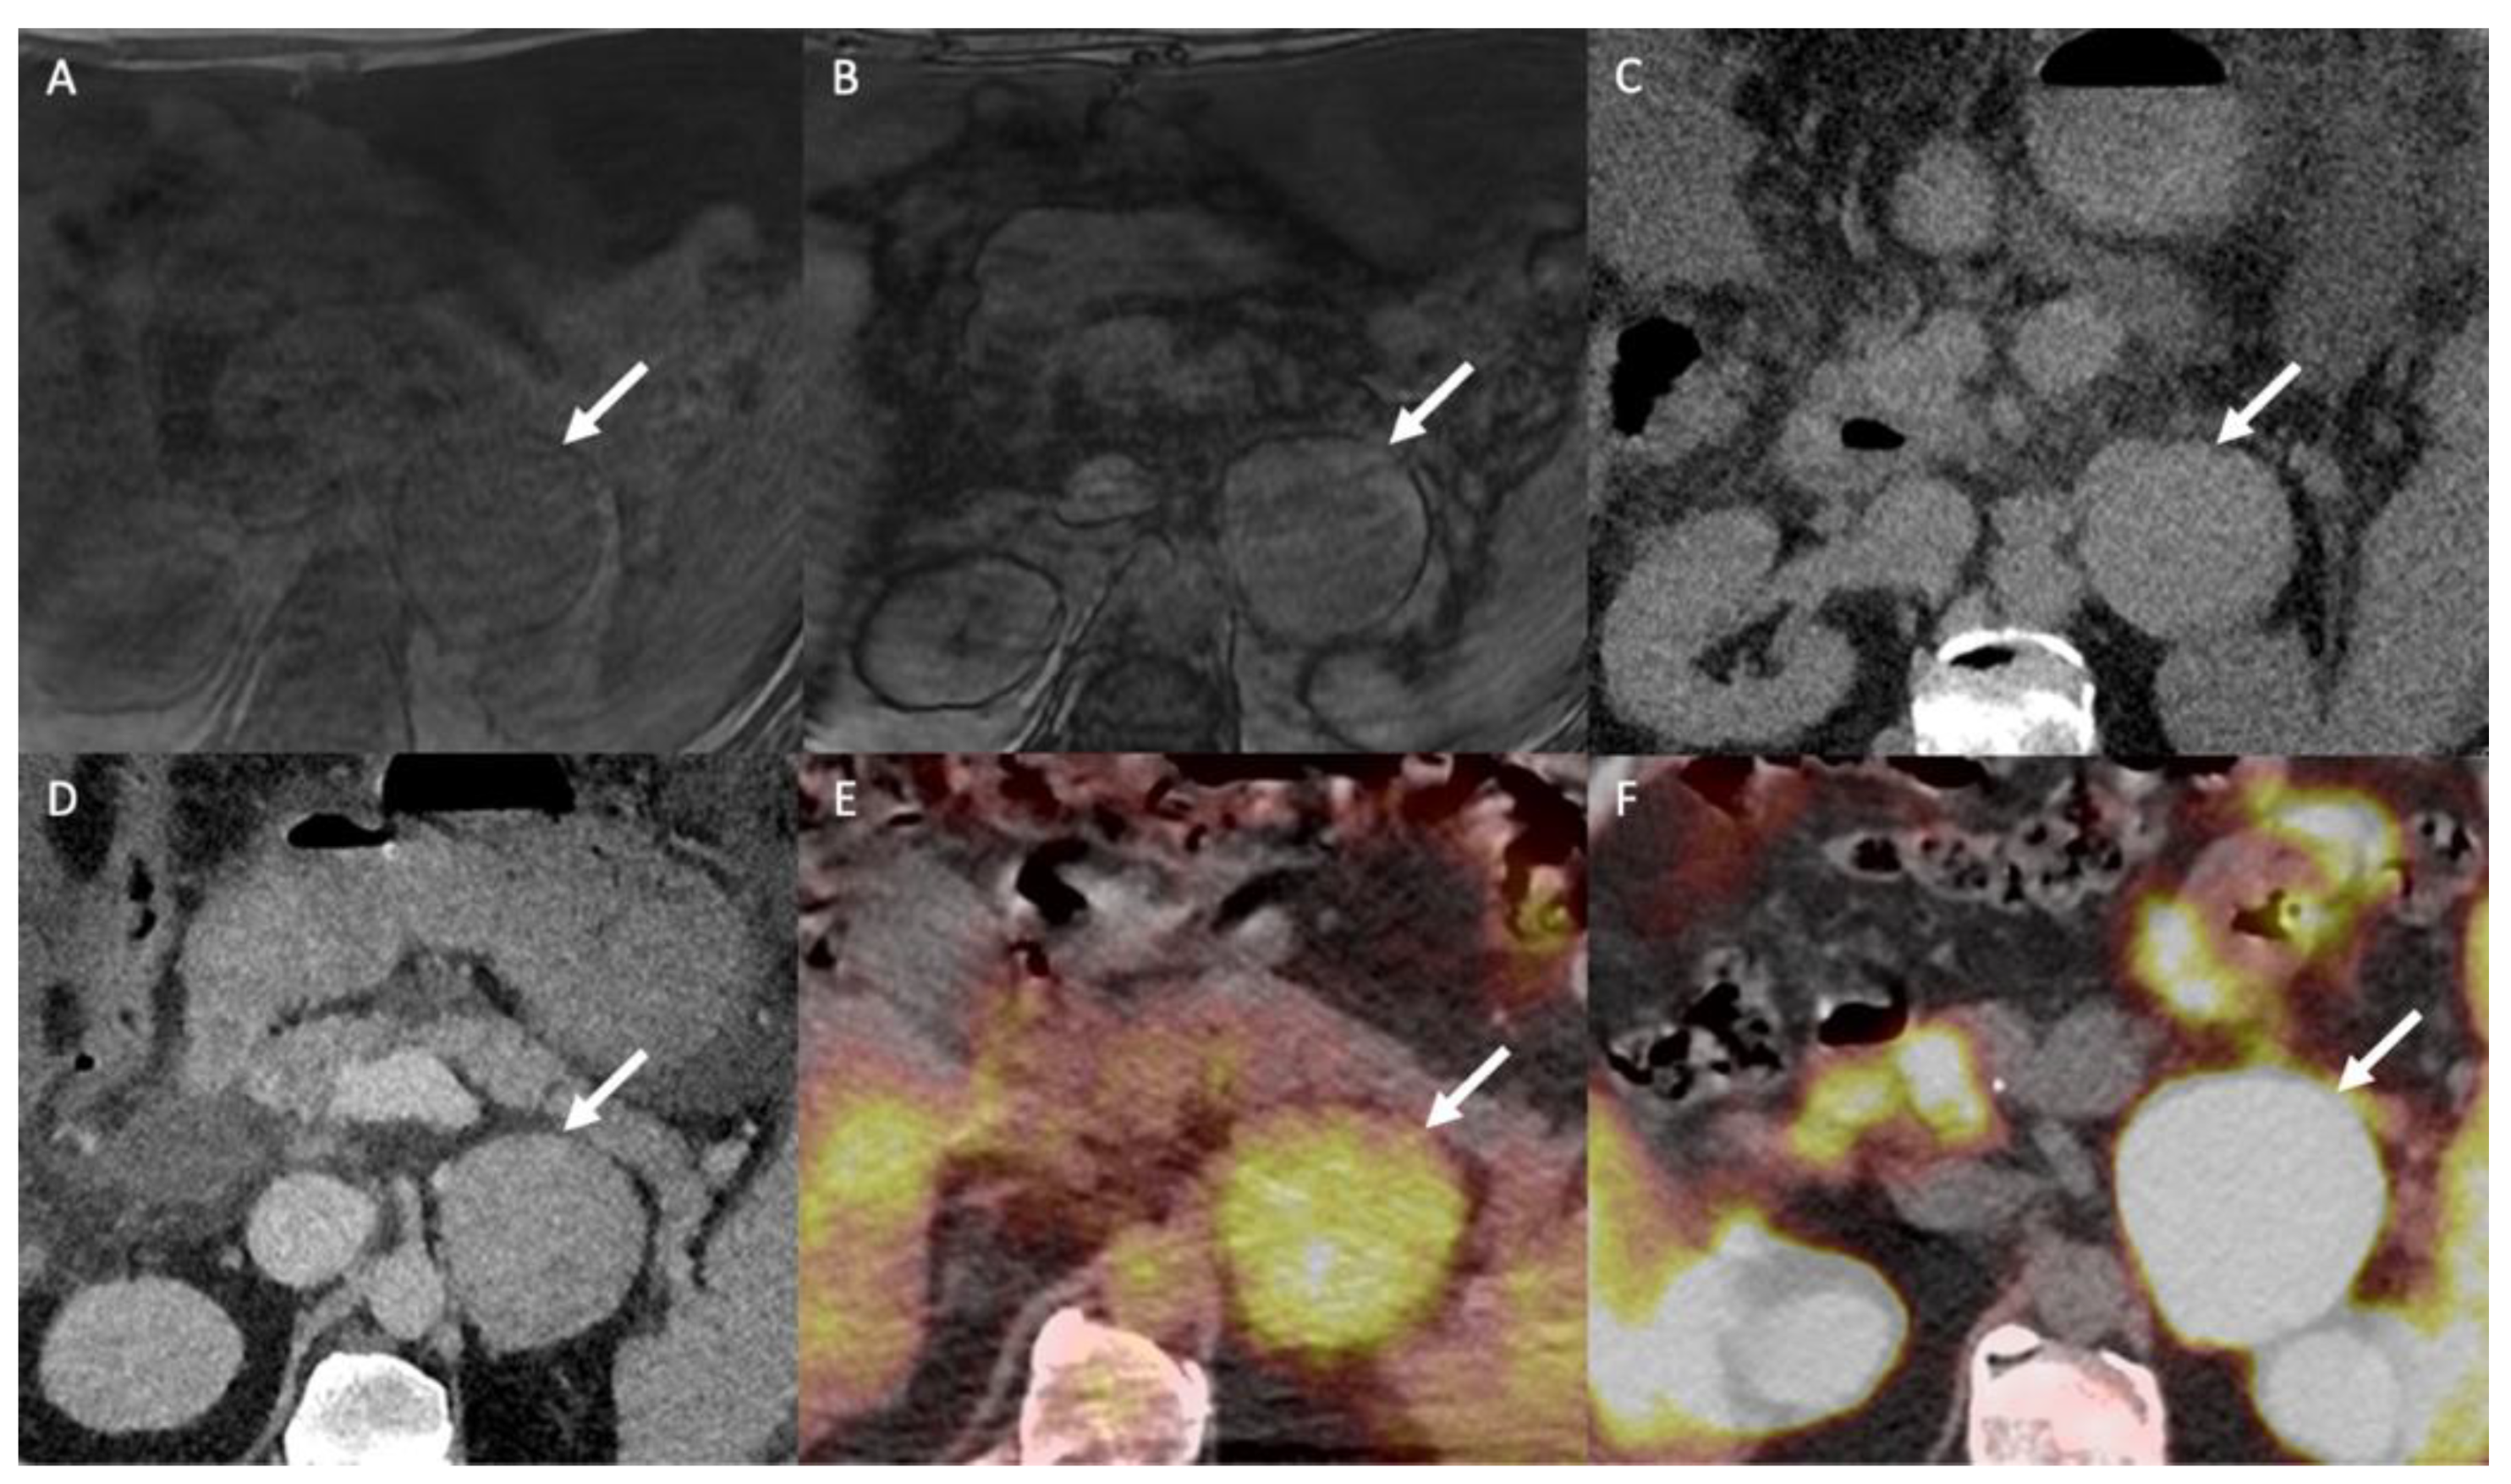

9.2. Magnetic Resonance Imaging

- Seo, J.M.; Park, B.K.; Park, S.Y.; Kim, C.K. Characterization of lipid-poor adrenal adenoma: Chemical-shift MRI and washout CT. Am. J. Roentgenol. 2014, 202, 1043–1050. [Google Scholar] [CrossRef]

- Haider, M.A.; Ghai, S.; Jhaveri, K.; Lockwood, G. Chemical shift MR imaging of hyperattenuating (>10 HU) adrenal masses: Does it still have a role? Radiology 2004, 231, 711–716. [Google Scholar] [CrossRef]

- Dixon, W.T. Simple proton spectroscopic imaging. Radiology 1984, 153, 189–194. [Google Scholar] [CrossRef]

- Platzek, I.; Sieron, D.; Plodeck, V.; Borkowetz, A.; Laniado, M.; Hoffmann, R.T. Chemical shift imaging for evaluation of adrenal masses: A systematic review and meta-analysis. Eur. Radiol. 2019, 29, 806–817. [Google Scholar] [CrossRef]

- Stanzione, A.; Verde, F.; Galatola, R.; Romeo, V.; Liuzzi, R.; Mainenti, P.P.; Aprea, G.; Klain, M.; Guadagno, E.; Del Basso De Caro, M.; et al. Qualitative Heterogeneous Signal Drop on Chemical Shift (CS) MR Imaging: Correlative Quantitative Analysis between CS Signal Intensity Index and Contrast Washout Parameters Using T1-Weighted Sequences. Tomography 2021, 7, 961–971. [Google Scholar] [CrossRef]